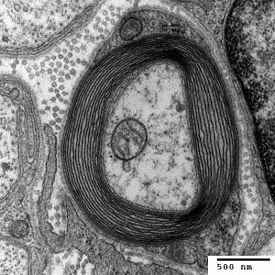

Myelin wird von Zellen gebildet: im Zentralnervensystem von Oligodendrozyten, im peripheren Nervensystem von Schwann-Zellen. Dass zentralnervöses Myelin von zellulären Fortsätzen der Oligodendrozyten gebildet wird, war lange umstritten und wurde erstmals 1962 von Mary Bartlett Bunge (* 1931) und Richard P. Bunge (1932–1996) in elektronenmikroskopischen Aufnahmen gezeigt. Myelin wird häufig als ein spezielles Merkmal der Wirbeltiere angesehen. Allerdings besitzen einige wirbellose Tiergruppen funktionale und strukturelle Analogien.